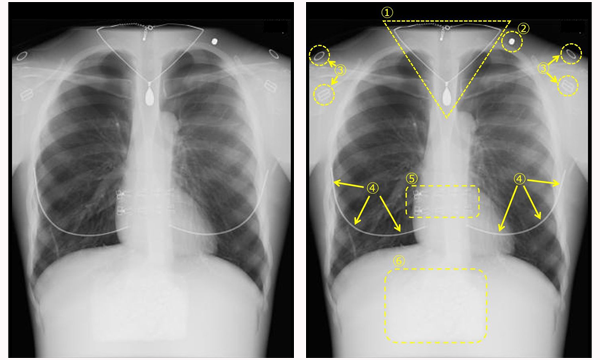

X線撮影では,X線が透過しやすいものほど黒く写り,透過しにくいものほど白く写ります。例えば空気を多く含んでいる肺はX線を透過しやすいので黒く写り,骨はX線を透過しにくいので白く写ります。医師はこの白黒の濃淡の差などを見て画像診断(読影)を行います。X線が透過しにくい素材の服装や装飾は,画像に白く写り込んでしまうためX線撮影時には適しません。

これらが観察したい部分と重なって白く写り込んでしまうと,異常を見つける機会を逃し,正確な診断ができなくなるおそれがあるのです。

金属類などが写り込んでいる胸部X線写真の例